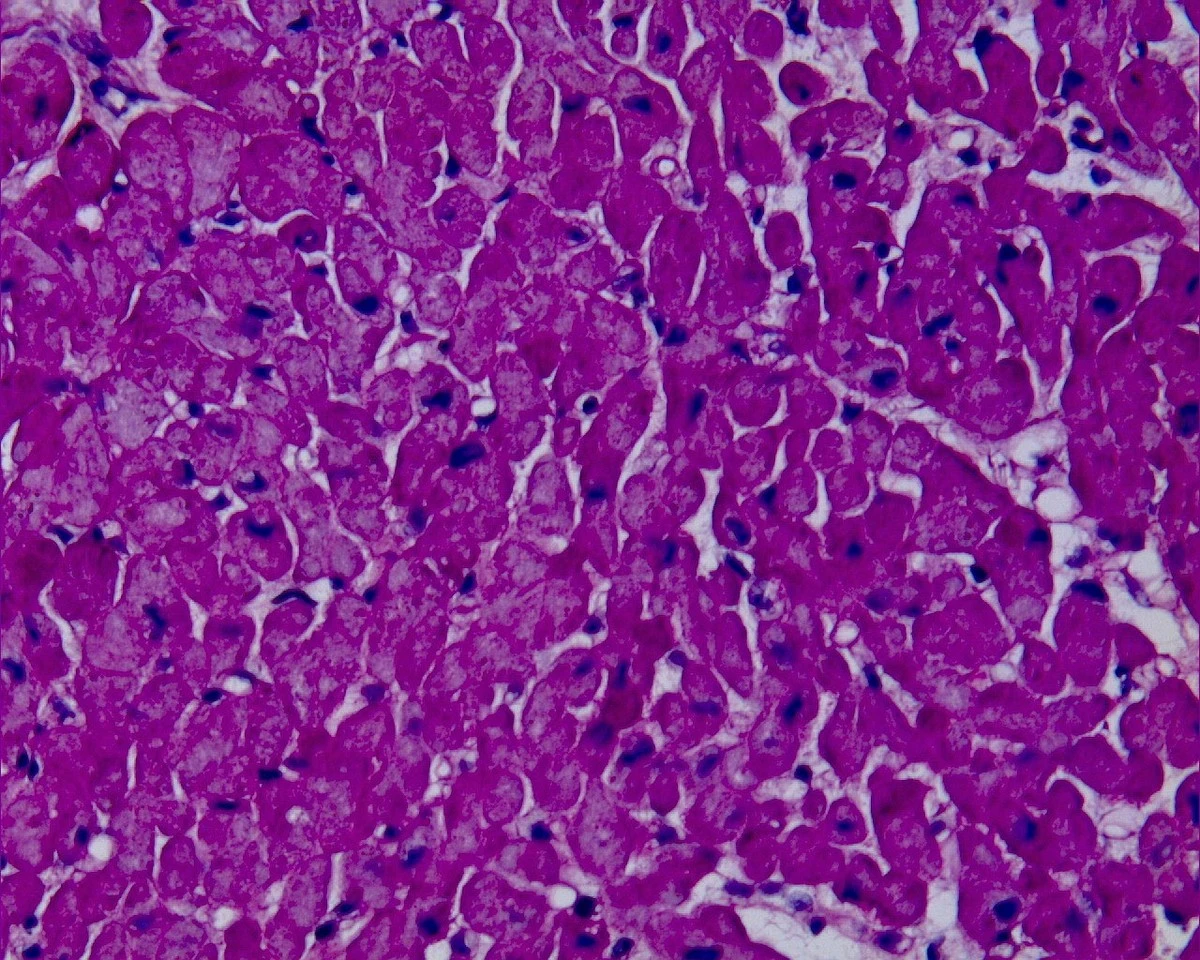

Při studiu tohoto problému jsem narazila na fascinující výzkum z britských univerzit. Vědci zjistili, že za blokádou mikrocirkulace stojí buňky zvané pericyty. Ty se po infarktu křečovitě stáhnou a nepustí krev dál. A právě tady nastupuje látka GLP-1, kterou dnes zná celý svět pod obchodními názvy jako Ozempic nebo Wegovy.

- Obnovuje průtok krve v kapilárách během několika minut po aplikaci.

- Minimalizuje trvalé poškození srdečního svalu.

Zatímco výzkum probíhal na myších srdcích, výsledky jsou natolik přesvědčivé, že se již mluví o klinickém testování u lidí. Tady je malý tip, co si z toho odnést už dnes: Pokud se léčíte s cukrovkou nebo obezitou a váš lékař vám tyto moderní léky předepsal, pamatujte, že vedlejším efektem může být i nečekaná ochrana vašeho srdce před budoucími komplikacemi.